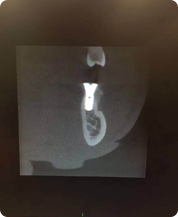

先来看一组CT

这是三个种植牙后在CT里面显现的影像种植牙效果选择

意大利Newton VCI 大视野CT

菲特口腔,拥有整套数字化设备及Newton VCI大视野CT,可以拍摄到整个头颅结构以便在种植牙位置选择上更精确,咬合才会好,数字化设备让种植牙手术从人为的判断到电脑的3D呈现,让手术效果可预知,更直观,更微创。